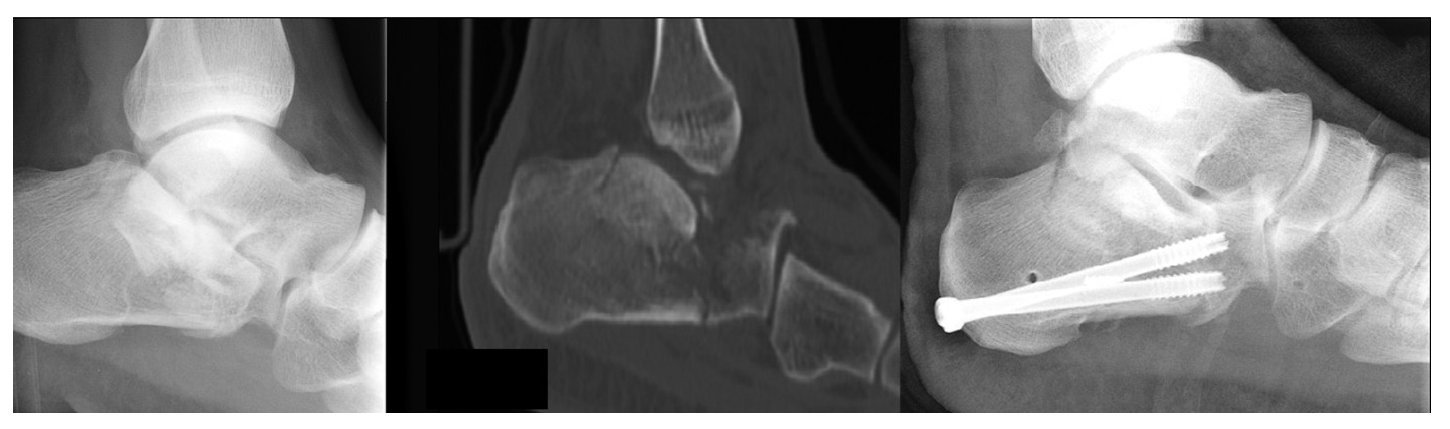

Entre 1999 y 2004 se trataron 59 pacientes con 71 fracturas mediante distracción ósea percutánea triangular22 (para ejemplos, ver figuras 7 a 9).

Figure 9 Caso 3: Un varón de 43 años de edad cayó desde una altura de 3 m sufriendo una fractura bilateral del calcáneo. En el lado izquierdo la fractura era en lengüeta de Essex-Lopresti y un tipo IIC de Sanders. Las radiografías a los 3 y 12 meses mostraban una buena resolución, pero el paciente tenía dolor y se le practicó una artrodesis subastragalina a los 14 meses.